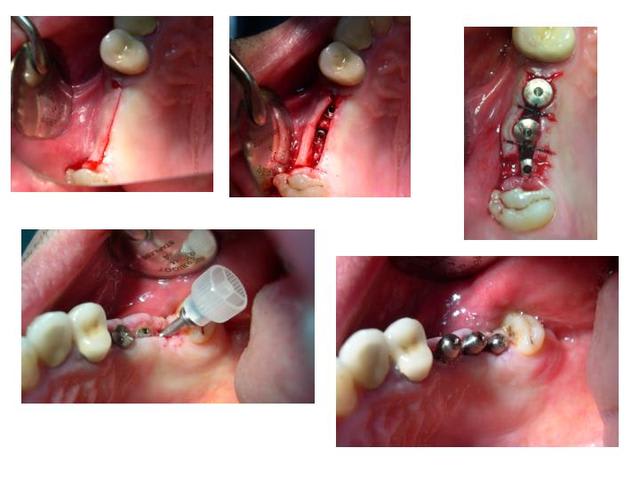

voilà, pour revenir à ce qu'on disait: une petite illustration: 25 et 27 ont été extraites. et voici la suite.

Fenêtre1 f7m7am - Eugenol

Fenêtre 2 qltvye - Eugenol

et la suite

Décollement membrane ljuoee - Eugenol

Implants iwsvxa - Eugenol

et encore

Comblement aujlvz - Eugenol

Sutures vzgxss - Eugenol